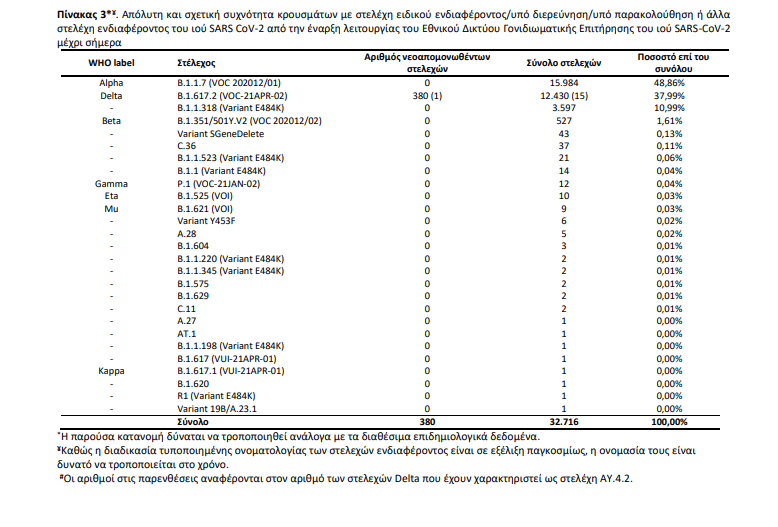

Πίνακας 3. Απόλυτη και σχετική συχνότητα κρουσμάτων με στελέχη ειδικού ενδιαφέροντος/υπό διερεύνηση/υπό παρακολούθηση ή άλλα στελέχη ενδιαφέροντος του ιού SARS CoV-2 από την έναρξη λειτουργίας του Εθνικού Δικτύου Γονιδιωματικής Επιτήρησης του ιού SARS-CoV-2 μέχρι σήμερα

Εκ των 380 δειγμάτων με στελέχη ειδικού ενδιαφέροντος, όλα αφορούν στο στέλεχος Delta (Πίνακας 3). Ένα εκ των 380 στελεχών Delta αφορά στο στέλεχος ΑΥ.4.2, το οποίο εντοπίστηκε σε δείγμα κρούσματος στην Περιφερειακή Ενότητα του Λασιθίου.

Από την έναρξη λειτουργίας του Εθνικού Δικτύου Γονιδιωματικής Επιτήρησης του ιού SARS-CoV-2 μέχρι σήμερα έχουν ελεγχθεί στην επικράτεια συνολικά 35.648 δείγματα από εγχώρια κρούσματα. Εξ αυτών 31.473 προέρχονται από τυχαία επιλογή δειγμάτων, 3.434 προέρχονται από στοχευμένη λήψη ή επιλογή δειγμάτων και για 741 δείγματα δεν είναι διαθέσιμος ο τρόπος επιλογής. Μεταξύ των 31.473 τυχαία επιλεγμένων δειγμάτων στην επικράτεια, τα τέσσερα πιο συχνά στελέχη ειδικού ενδιαφέροντος ή υπό παρακολούθηση που έχουν απομονωθεί είναι το Alpha, με ποσοστό 49,45%, ακολουθούμενο από το Delta με ποσοστό 35,20%, το B.1.1.318 (Variant E484K) με ποσοστό 7,44%, και το Beta με ποσοστό 1,06% (Πίνακας 4).

Από τα δείγματα αυτά, 38,15% αφορούν στο B.1.1.318 (Variant E484K), 35,12% στο Delta, 15,70% στο Alpha, 5,88% στο Beta, 0,12% στο C.36, 0,09% στο Gamma, 0,09% στο Eta και 0,09% στο A.28.

Επιπλέον, έχουν απομονωθεί συνολικά 382 στελέχη ειδικού ενδιαφέροντος ή υπό παρακολούθηση ή ενδιαφέροντος από δείγματα εισαγόμενων κρουσμάτων, εκ των οποίων 248 αφορούν στο Delta, 113 στο Alpha, 7 στο Mu, 6 στο Beta, 4 στο B.1.1.318 (Variant E484K), 1 στο Eta, 1 στο C.36, 1 στο Kappa και 1 στο B.1.1 (Variant E484K). Όσον αφορά στα στελέχη ενδιαφέροντος που χρήζουν άμεσης λήψης μέτρων ελέγχου επί του παρόντος στη χώρα, η γεωγραφική κατανομή ανά Περιφερειακή Ενότητα παρουσιάζεται στον πίνακα 5.